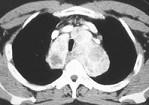

男,41岁,体检X线提示纵隔增宽,CT检查如图,请选出最可能的诊断 ( )A.淋巴瘤B.纵隔畸胎瘤C.胸腺瘤D.间皮囊肿E.胸内甲状腺肿

问题 男,41岁,体检X线提示纵隔增宽,CT检查如图,请选出最可能的诊断 ( )

选项 A.淋巴瘤 B.纵隔畸胎瘤 C.胸腺瘤 D.间皮囊肿 E.胸内甲状腺肿

答案 E